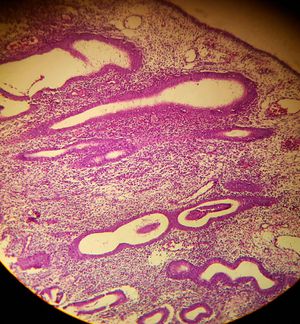

Dont remember much from pathology course but it looks like epothelium in a wrong place ... So it will be 1

We can rule out other two.... In bph the glands have two layers of cells just like in normal prostate.. Just there no is inc..... While in teratoma you can see different types of tissue like muscle.. Bone.. Nerve.. Gland etc... Here we don't see that... So its end hyp